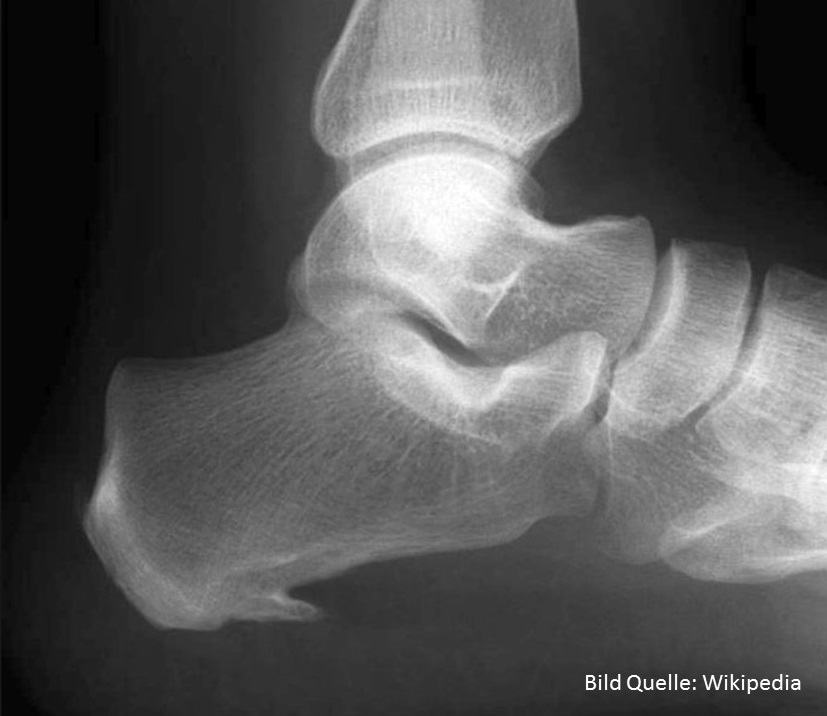

Sportverletzungen - Das verletzte Sprunggelenk

Eine der häufigsten Verletzungen im Sport betrifft das Sprunggelenk. Bänderrisse, Überdehnungen usw. sorgen dafür, dass Sportler zum Teil langfristig verletzt sind. Im Gastbeitrag von Dr.med. Niklas Renner, Facharzt für Orthopädie und Traumatologie des Bewegungsapparates FMH kannst du viel Wissenswertes über dein Sprunggelenk erfahren.